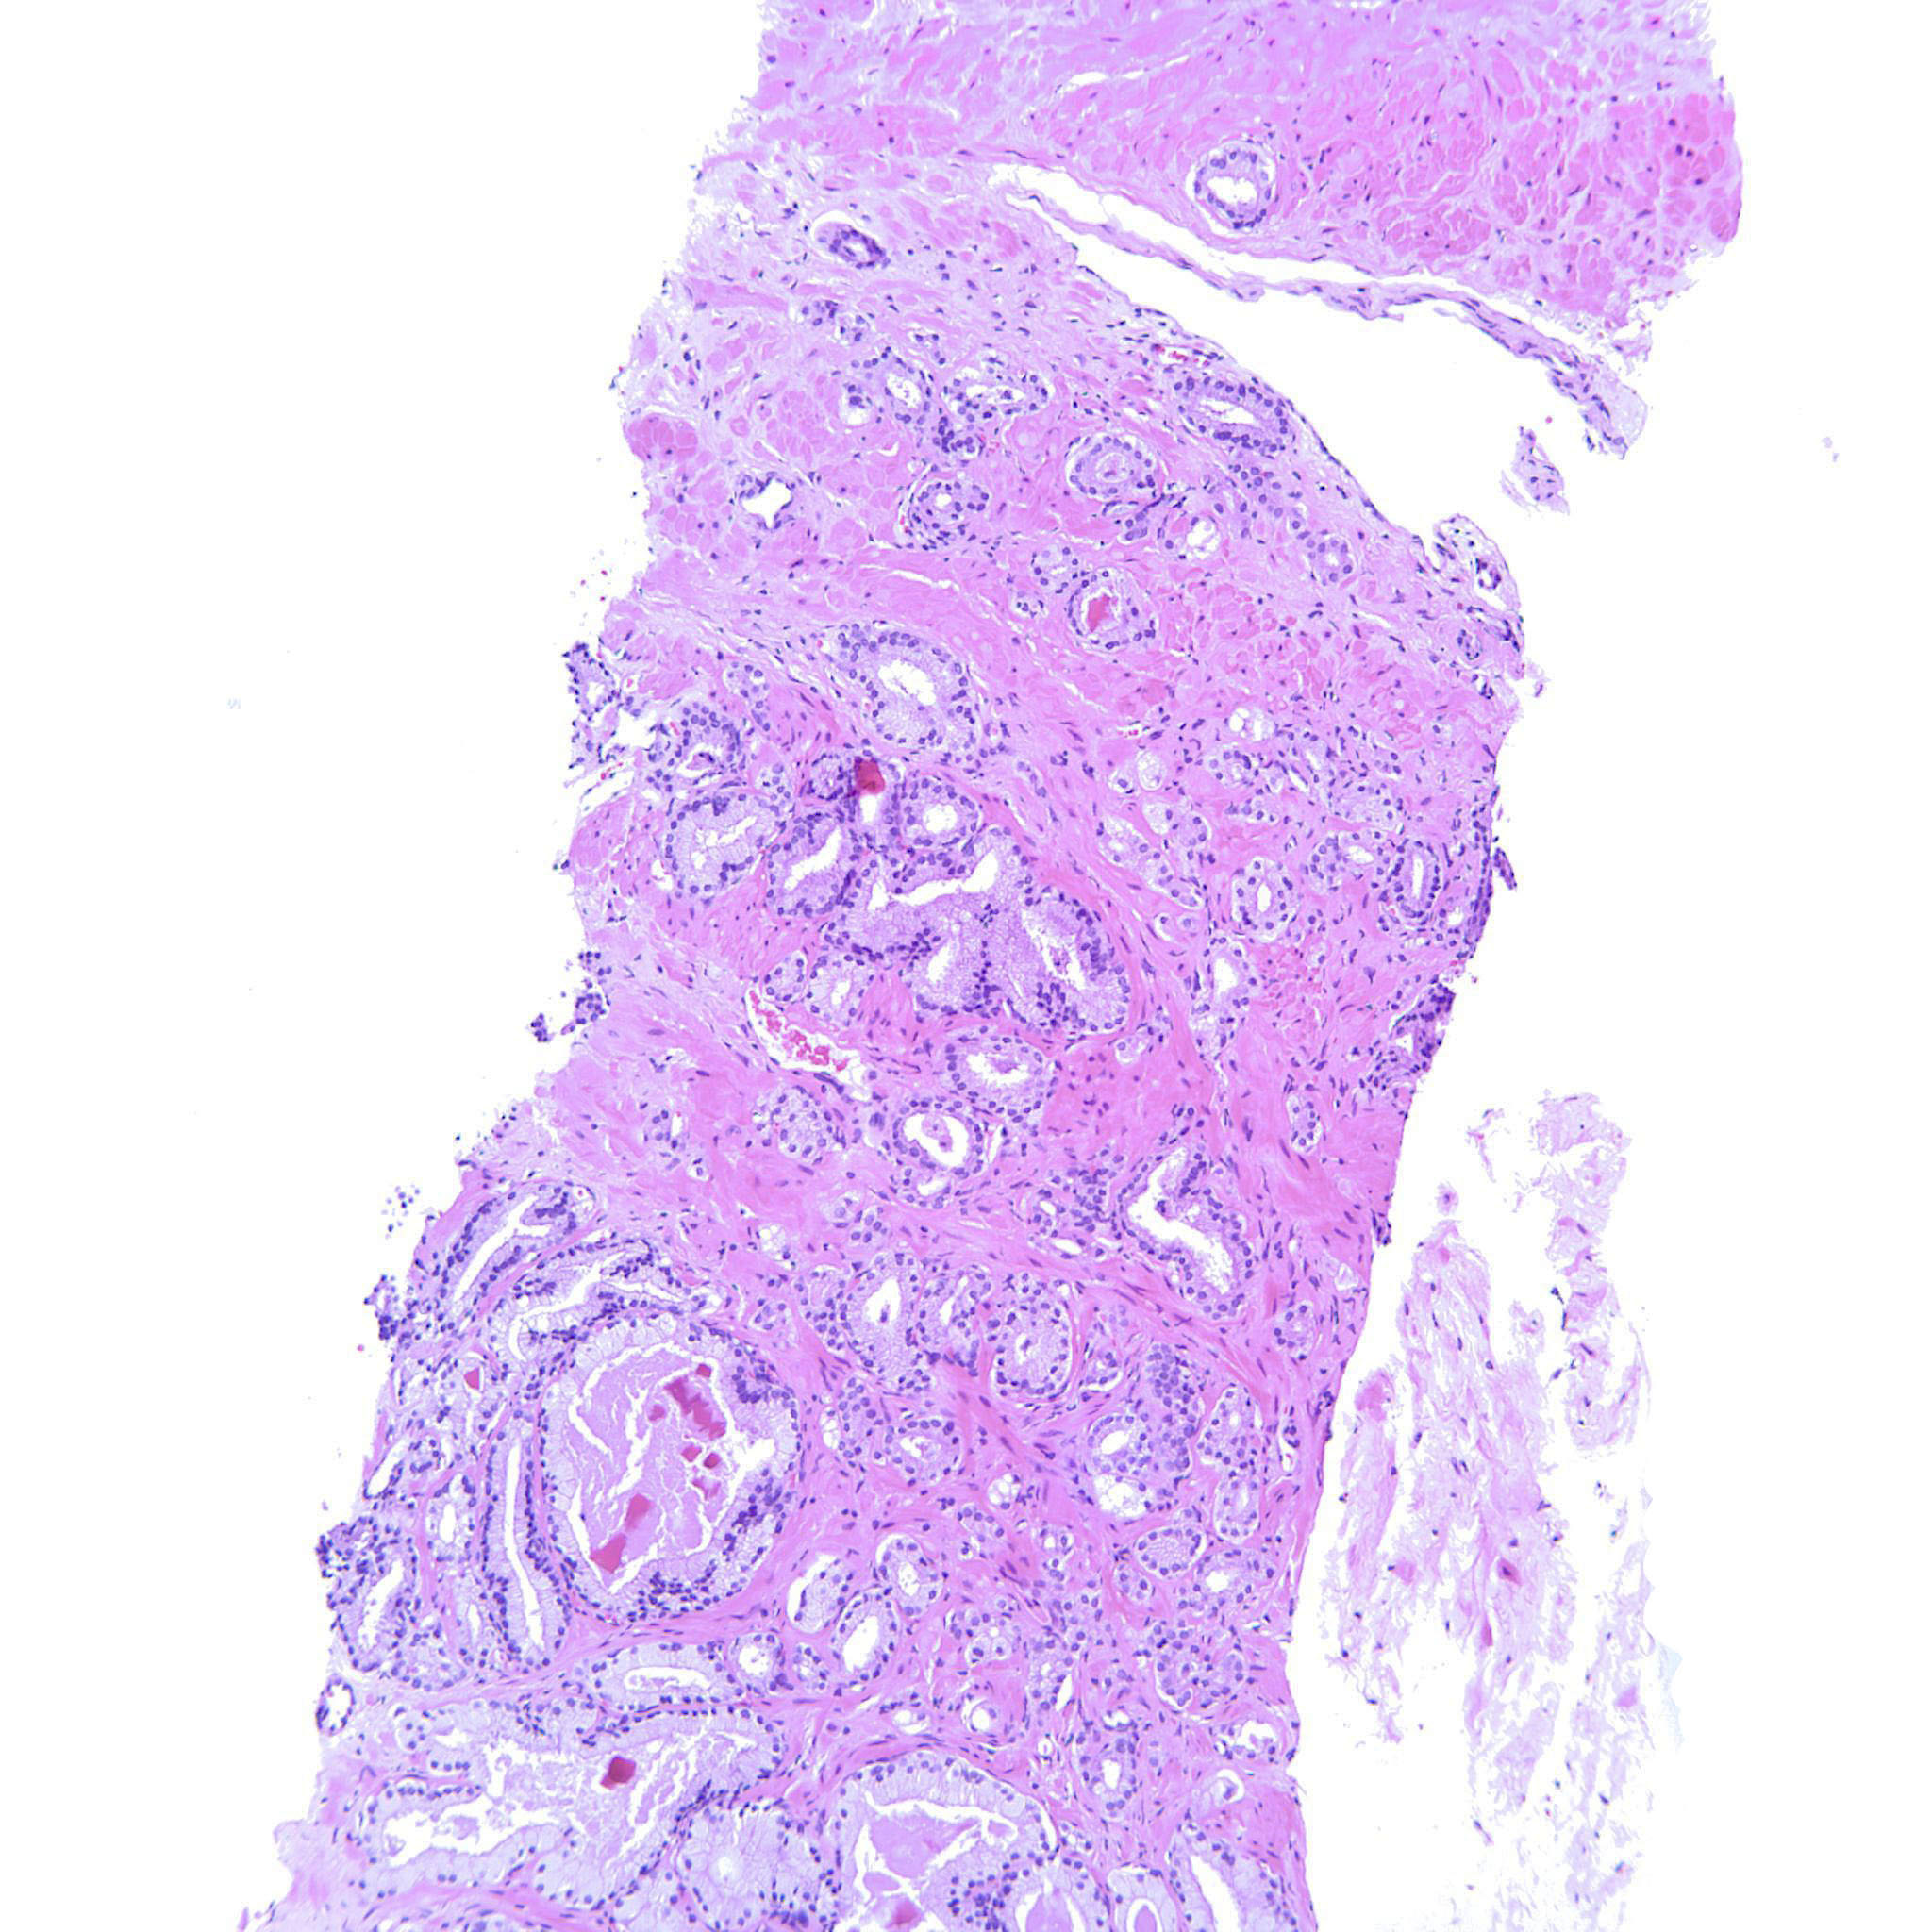

Case ID: 768

Consensus grade: GS 3+4=7 (ISUP 2)

Case description (by case creator):

Most of the tumor is GP3 but there are also some poorly formed glands.